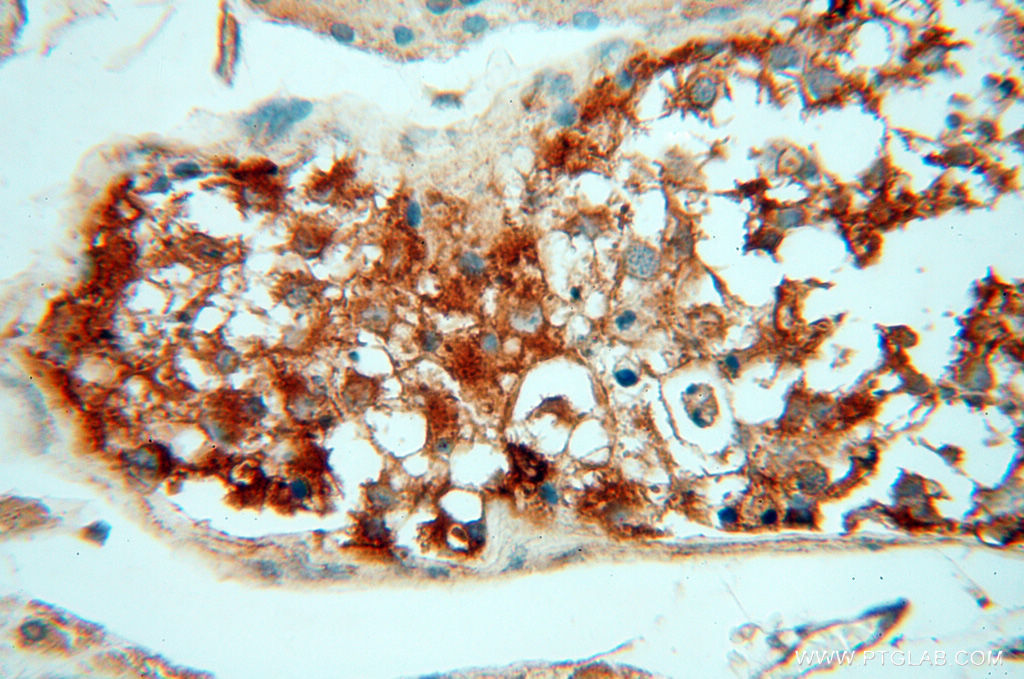

Supportive validation

- Submitted by

- Proteintech Group (provider)

- Main image

- Experimental details

- Immunohistochemical of paraffin-embedded human testis using 14555-1-AP(tubulin-Alpha antibody) at dilution of 1:50 (under 10x lens)

- Sample type

- tissue

- Immunohistochemical of paraffin-embedded human testis using 14555-1-AP(tubulin-Alpha antibody) at dilution of 1:50 (under 40x lens)